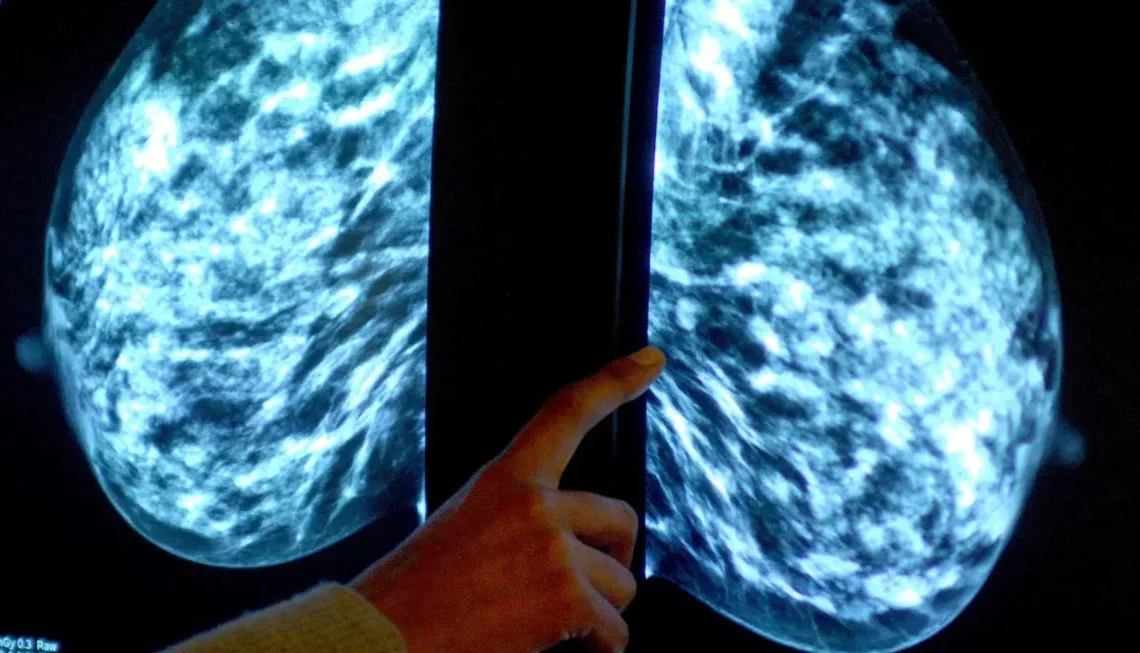

El informe está contenido en el boletín epidemiológico de la Semana 03 del Ministerio de Salud Pública, que destaca que entre los mayores casos está el cáncer de mama con 2,070, en ese período, cáncer de próstata, que ocupa el segundo lugar con 1,249 casos, cáncer de cérvix, que registra 728 casos, cáncer colorrectal con 573 casos detectados y Leucemia con 440 casos que afectan a ambos sexos.

Asimismo, se reportó una carga relevante en cáncer de pulmón (317 casos) y cánceres ginecológicos como endometrio (197) y ovario (84).

Además, incluyen otros no especificados con 673 casos.